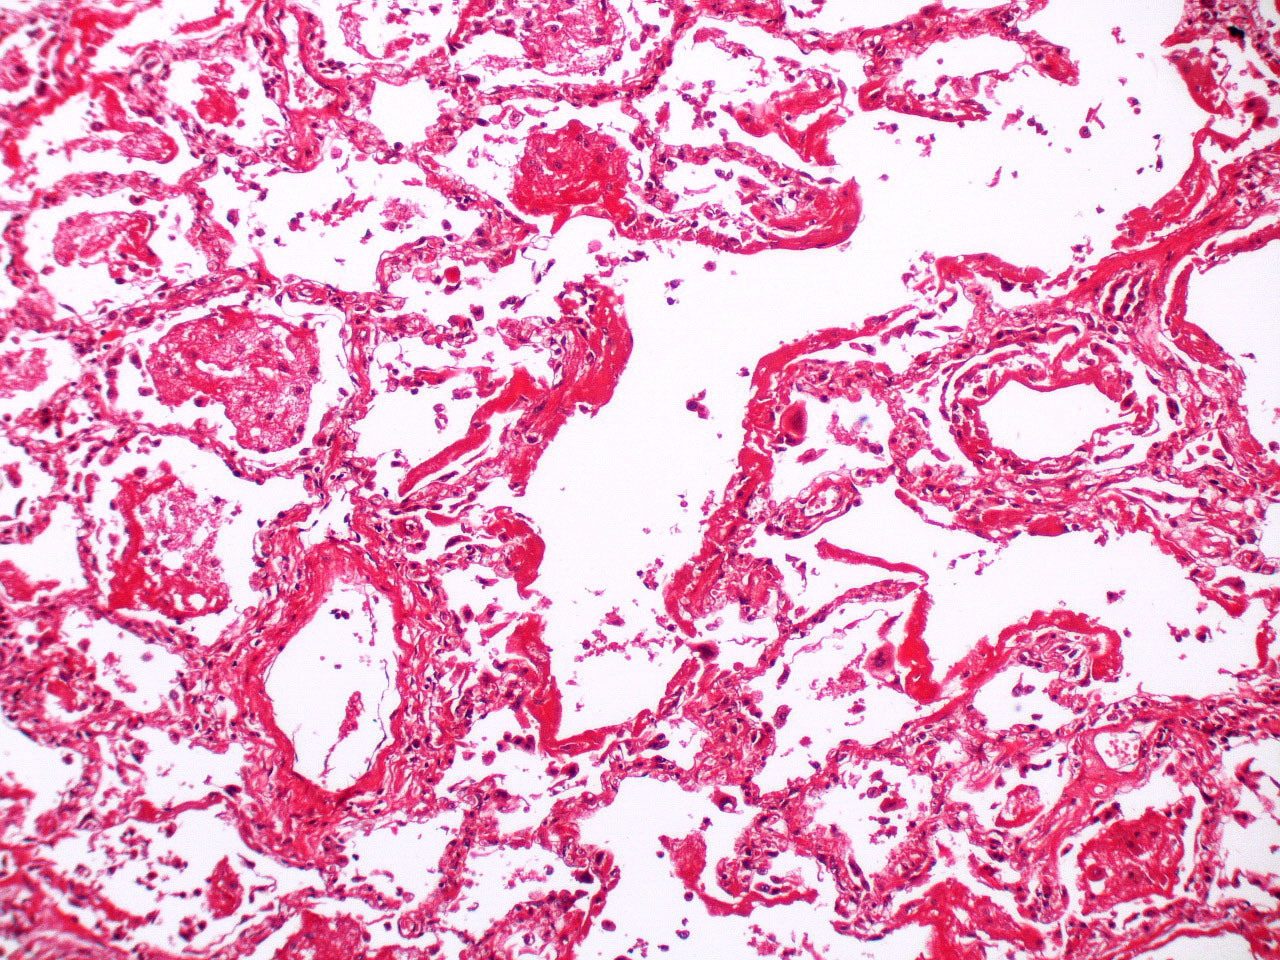

Microscopic (histologic) description

- Histopathology of DAD progresses from exudative (acute) phase through proliferative / organizing (subacute) phase to chronic fibrotic phase roughly corresponding to the period of ARDS (Am J Pathol 1976;85:209, Arch Pathol Lab Med 2010;134:719, Clin Chest Med 2000;21:435, N Engl J Med 2000;342:1334)

- Proliferative / organizing (subacute) phase

- Alveolar change

- Remnants of hyaline membrane with or without organization

- Interstitial and intra-alveolar proliferation of myofibroblasts

- Lymphocytic infiltration

- Epithelial change

- Proliferation / hyperplasia of type II pneumocytes

- Vascular change

- Endothelial injury and thromboemboli in arterioles

- Alveolar change

- Fibrosis phase

- Alveolar change

- Collagenous fibrosis

- Microscopic honeycomb-like change

- Traction bronchiolectasis

- Epithelial change

- Squamous metaplasia / hyperplasia

- Vascular change

- Remodeling of arteries

- Intimal fibrosis

- Thickening of media

- Alveolar change

Microscopic (histologic) images

Contributed by Akira Yoshikawa, M.D. and Yale Rosen, M.D.